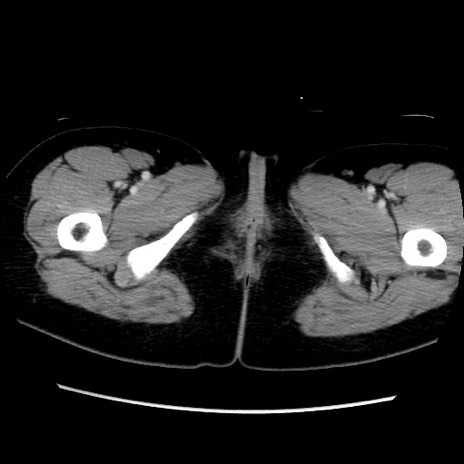

MRI(4日後)

【症例】40歳代女性

【主訴】上下腹部痛

【現病歴】2日目から下腹部痛あり。夜間は痛みで眠れなかった。昨日より上腹部痛と下痢が出現。臥位で痛みは軽快したため、休んでいた。本日になって臥位でも立位でも痛みが強くなってきたため救急要請。

【既往歴】子宮内膜症

【身体所見】部:平坦・軟、左上下腹部に圧痛あり、反跳痛あり。

【データ】WBC 21800、CRP 26.78